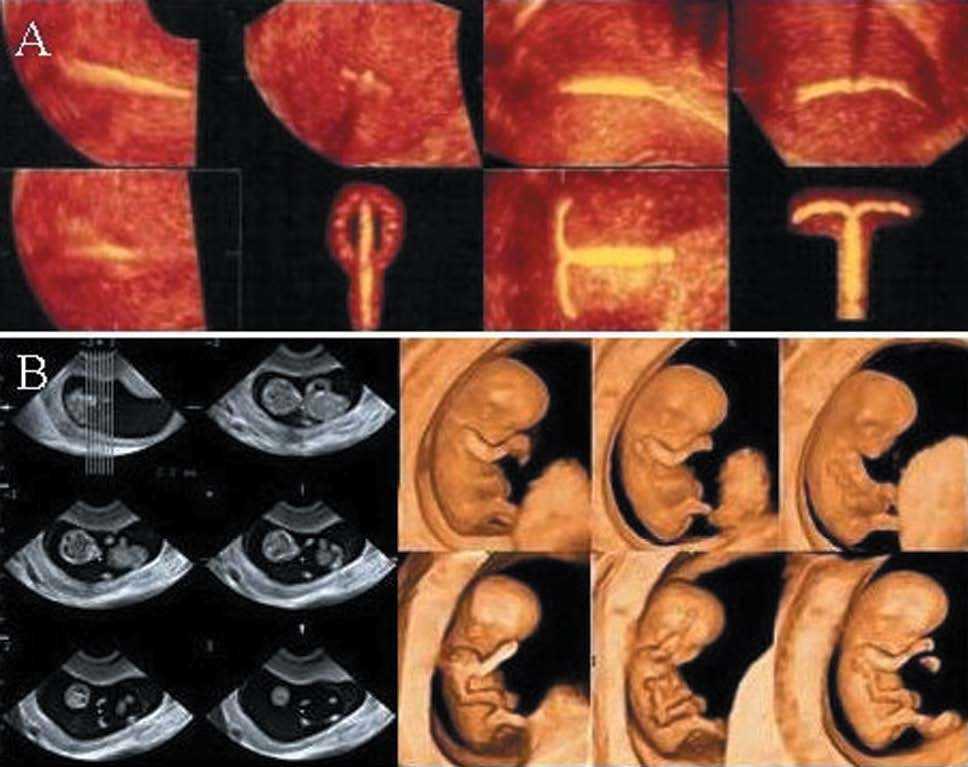

-- STIC: volumen 4D usando el software de correlación de imágenes espacio-temporales. Permite capturar el ciclo completo del latido del corazón del feto en tiempo real y guardar el volumen para el análisis posterior correlativo con el electrocardiograma (fig. 1A).

Figura 1.A) Reconstrucción 3D-4D de los arcos aórtico y ductal. STIC modo inverso. B) imagen B-Flow del arco aórtico. (Cedido gentilmente por General Electric.)

DeVore7, en el año 2003, describe el STIC. El volumen adquirido se estudió en un ciclo cardíaco repetitivo gracias al cine loop, y presentado en forma lenta para ver las diversas fases del ciclo cardíaco, las cámaras del corazón, las válvulas, el septo y el tracto del flujo de salida, sin aumentar la duración del examen. En modo superficie, permitió establecer diagnósticos de las alteraciones de la superficie y de las cámaras cardíacas11.

Al agregar al STIC, TIU, Doppler color, power o flujo B, se ha podido observar la representación hemodinámica, lo que facilita la demostración de los flujos durante un ciclo cardíaco en los diferentes planos seccionales escogidos11 (fig. 1A y B)

La representación del STIC con body glass mode, es ideal para demostrar la relación espacial o las diferencias de tamaño de los grandes vasos conectados con el defecto del septo ventricular, el cruce de los grandes vasos, la transposición de las grandes arterias o el origen de la arteria subclavia aberrante (fig. 6B).